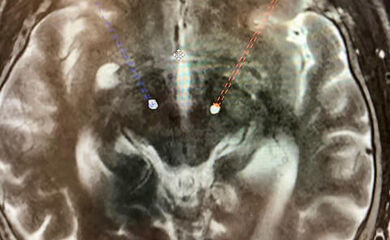

- Kernspintomographie des Kopfes. Wenn Sie aufgrund Ihrer Erkrankung Schwierigkeiten haben, für die Dauer der Unersuchung still zu liegen, wird diese ggf. in Narkose durchgeführt.

Die Elektroden für die Tiefe Hirnstimulation werden in einem sog. stereotaktischen Eingriff eingesetzt. Hierbei handelt es sich um ein minimalinvasives Operationsverfahren, bei dem Ihr Kopf in einem Stereotaxierahmen, eine Art Ring um den Kopf, fixiert wird. So wird ein Verwackeln verhindert und die Elektroden können computergestützt wie in der vorangegangenen MR-Planungsbildgebung geplant millimetergenau platziert werden. Noch im Operationssaal wird computertomographisch anschließend die korrekte Lage der Elektroden überprüft.

Hierbei wird ein Stereotaxierahmen zur OP am Kopf angebracht und eine spezielle CT-Bildgebung durchgeführt, die es erlaubt im Abgleich mit dem präoperativen Planungs-MRT den sicheren Weg von der Hirnoberfläche bis in die gewünschte Zielregion in Einstellungen für das millimetergenaue Setzen der Elektroden zu übersetzen.